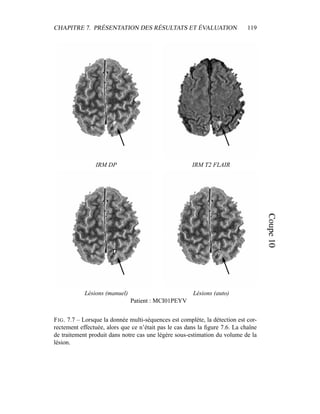

.

L’ensemble des points Ip forme un axe, dont le vecteur de progression est

−→

δIp.